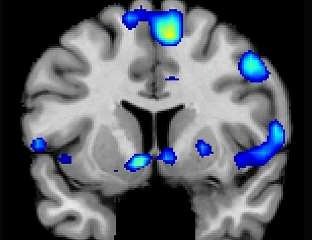

Религиозные и духовные переживания активируют центр вознаграждения (удовольствия) головного мозга, как и любовь, секс, азартные игры, наркотики и музыка, сообщают исследователи из школы медицины Университета штата Юта. Результаты опубликованы 29 ноября в журнале «Social Neuroscience».

На основании МРТ сканирования исследователи выяснили, что сильные духовные чувства связаны с активацией центра удовольствия в головном мозге. Как только участники испытывали пиковые ощущения, их сердца бились быстрее, и дыхание становилось глубже.

Кроме того, исследователи обнаружили, что духовные чувства связаны с медиальной префронтальной корой, которая представляет собой сложную область мозга, активирующую задачи, связанные с оценкой, суждением и моральными принципами. Также происходит активизация участков мозга, связанных со вниманием.